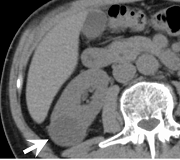

術前CT精査の例(腎細胞癌)

術前精査では、組織診断を推定するための造影 dynamic study(図1-4)と体幹部を含めたスキャンによる病期診断、また、手術シュミレーションに活用できる立体像(図5,6)作成を行っています。

| 図1 造影前CT 病変は腎実質よりも低吸収である |

図2 造影 dynamic CT 動脈相 病変は不均一な造影効果を示す |